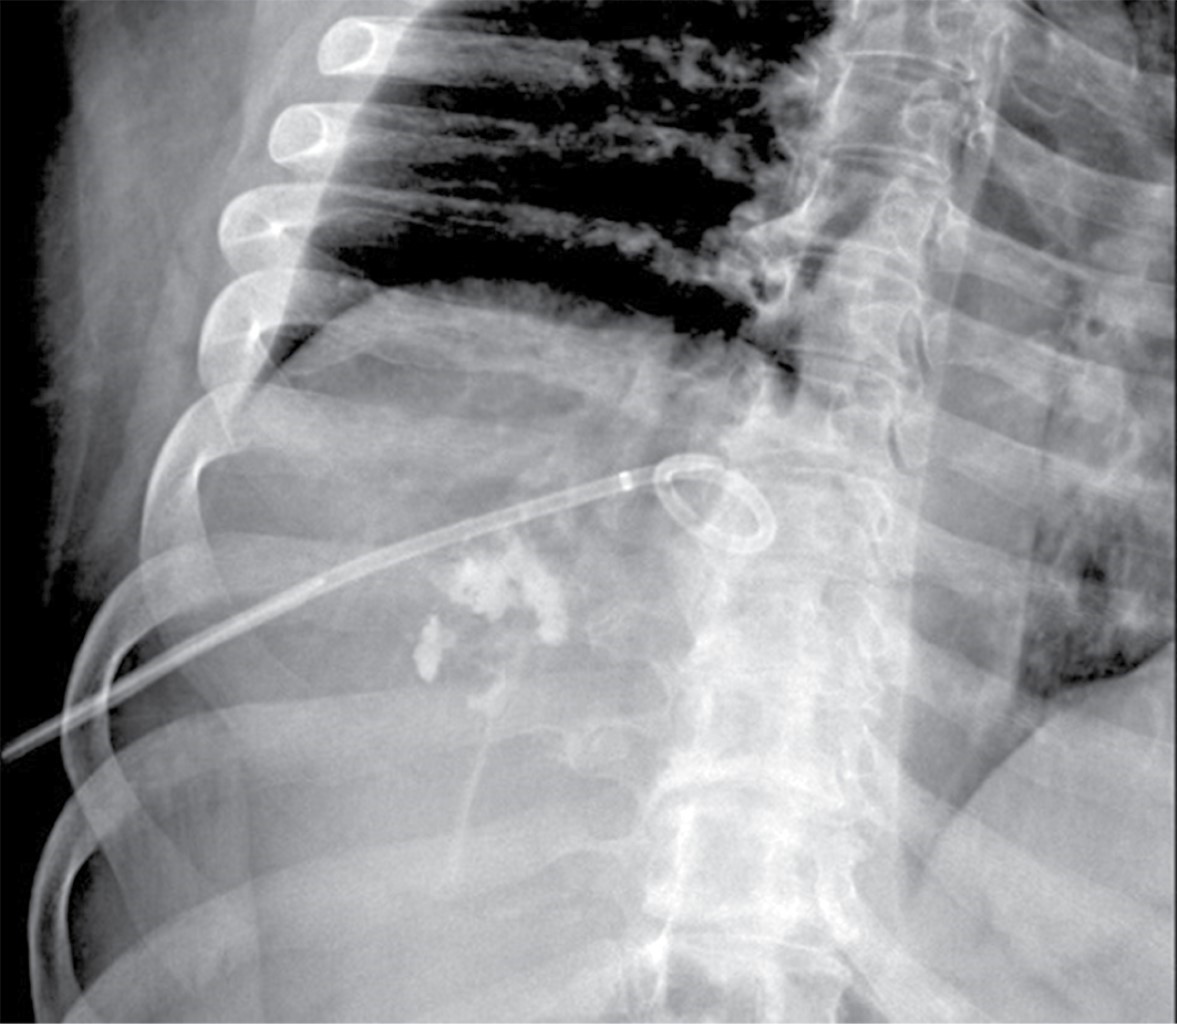

Posteriormente se realizó drenaje hepático por radiología intervencionista, obteniendo material purulento que en el cultivo reportó Streptococcus viridans (Figura 3). Asimismo, se dio manejo médico para el proceso inflamatorio apendicular, el cual no requirió quirúrgico.

Figura 3